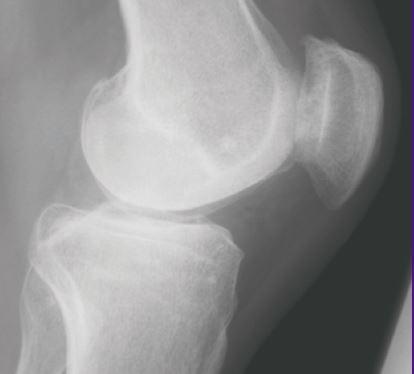

A new review by David A. Walsh and Joanne Stocks in the September 2017 issue of SLAS Discovery (formerly the Journal of Biomolecular Screening ) explores evolving treatments and future therapies for osteoarthritis (OA) pain.

It covers the limitations of existing treatments and introduces the latest understanding of the complex mechanisms behind OA pain, which offers exciting new possibilities and potential new treatment targets. Recent patents registered suggest that areas of future OA therapies could target inflammation, bone and cartilage; sensory nerves; tissue engineering and dietary supplements.

OA is the most common form of arthritis, yet unfortunately, the most effective treatment currently available for improving quality of life is total joint replacement.